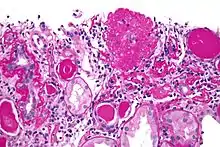

| Light micrograph of focal segmental glomerulosclerosis, hilar variant. Kidney biopsy. PAS stain. | |

On histology, FSGS manifests as damage (sclerosis) to segments of glomeruli; moreover, only a portion of glomeruli are affected.[19][20] The focal and segmental nature of disease seen on histology help to distinguish FSGS from other types of glomerular sclerosis.[20]

Diagnosis of FSGS is made by renal biopsy that includes at least 15 serial cuts with at least 8 glomeruli.[30][31] Histologic features include sclerosis (scarring) of a portion (average: 15%) of the glomerular space, with only a portion of glomeruli manifesting any sclerosis.[31]